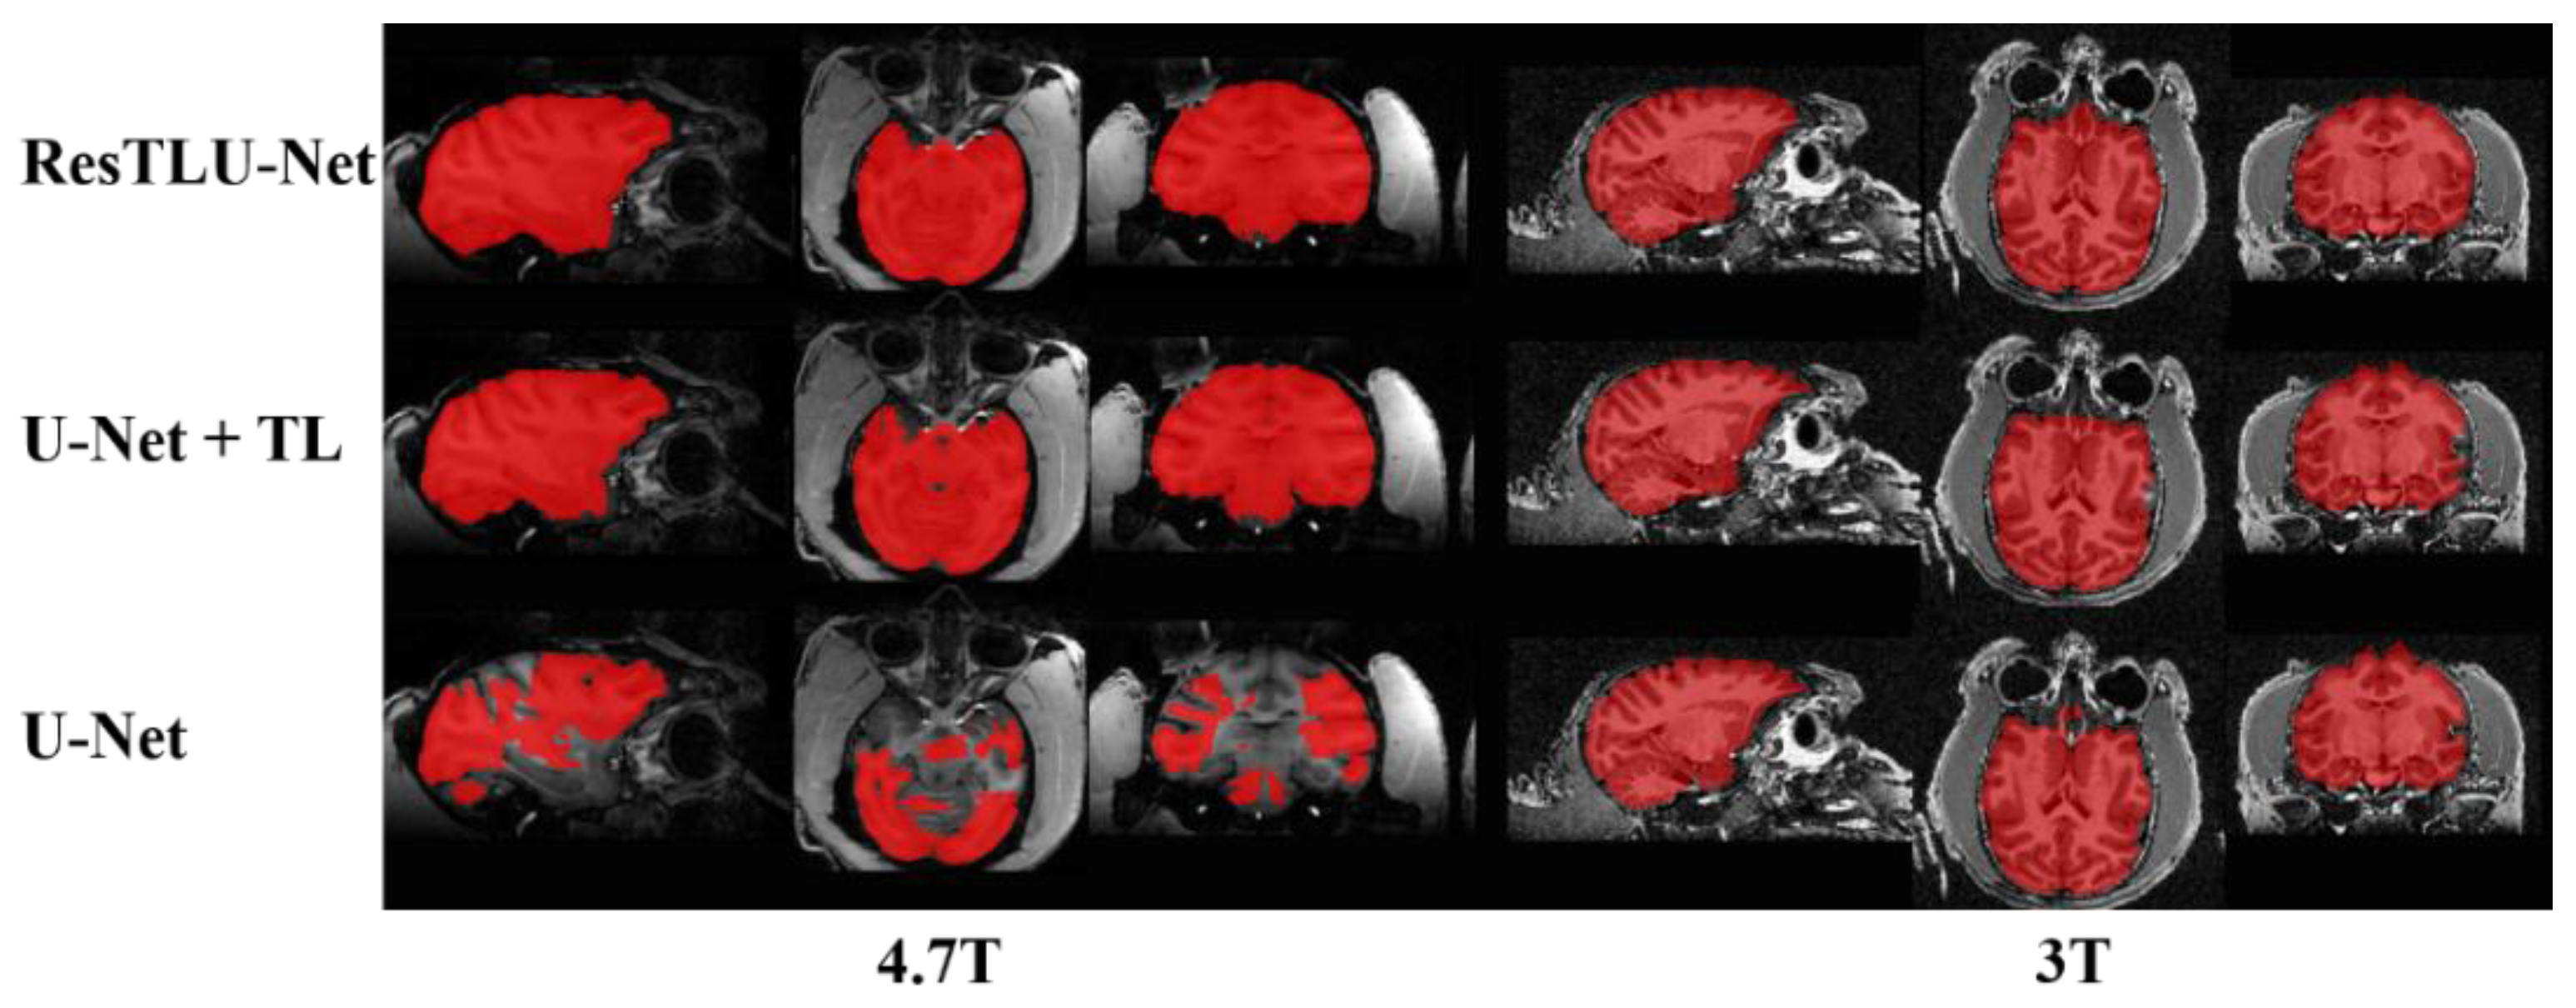

3.1. Comparsion of U-Net and ResTLU-Net

3.2. Verification of the Validity